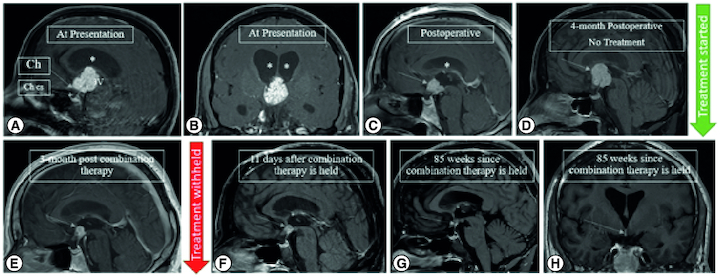

颅咽管瘤是由鼻咽部到间脑的 Rathke's 袋残余部分产生的肿瘤。目前的治疗标准包括最大限度的手术切除,以及在无法进行最大限度切除的情况下进行辅助放射治疗。对于 BRAF V600E 突变的肿瘤,使用 MAPK 靶向药物进行药物治疗是一种新兴的治疗方法。我们报告了一名 45 岁男性患者,他患有 BRAF V600E 突变的严格意义上的第三脑室乳头状颅咽管瘤。在初次手术进行次全切除后,患者对 BRAF 和 MEK 抑制剂(维莫非尼和克比米替)的靶向治疗产生了持久的反应。我们的报告表明,靶向治疗可以减少放射治疗的需求,并对特定病例的手术干预产生影响。

Craniopharyngiomas are tumors that arise from the remnants of Rathke's pouch along the nasopharynx to the diencephalon. Current standard of care includes maximal surgical resection versus adjuvant radiation if a maximal resection is unfeasible. Pharmacological therapy with MAPK targeted agents is an emerging therapeutic option for tumors with BRAF V600E mutations. We report a 45-year-old male with a strictly third ventricle papillary craniopharyngioma with a BRAF V600E mutation. After initial surgery with subtotal resection, the patient demonstrated durable response to targeted BRAF and MEK inhibitor therapy with vemurafenib and cobimetinib. Our report suggests that targeted therapy may reduce the need for radiation and impact surgical interventions in select cases.